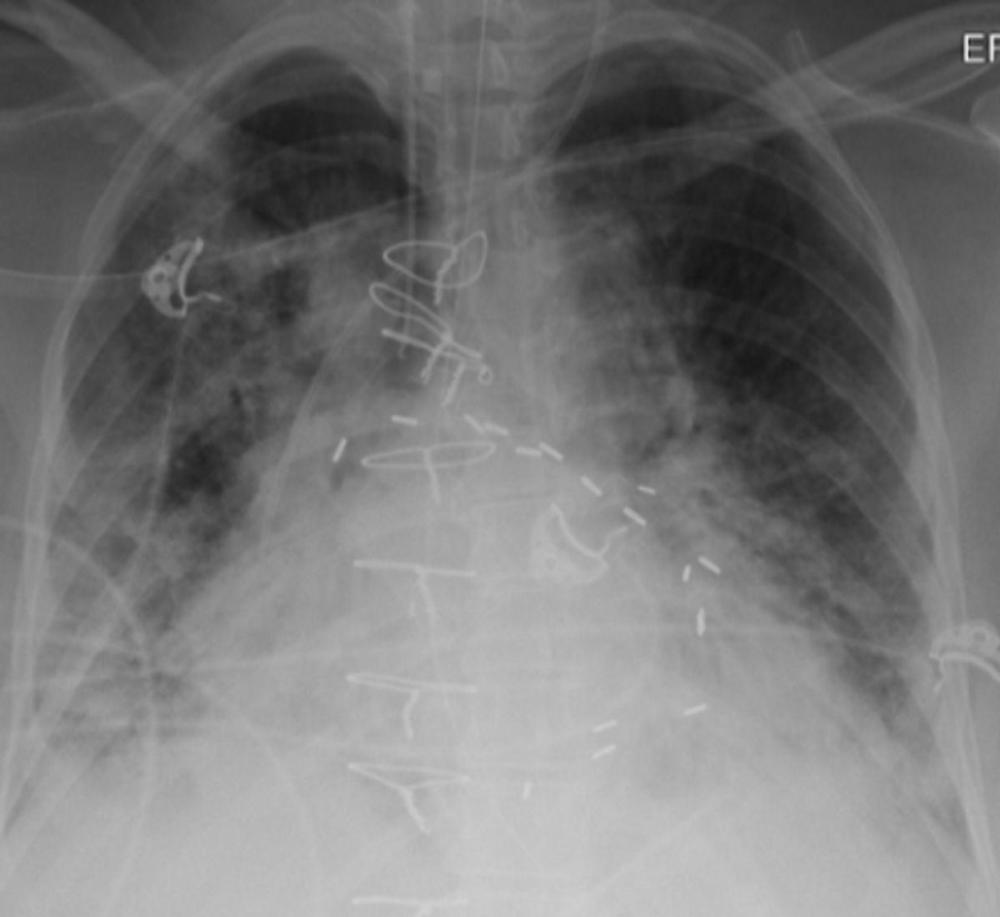

Figure 5. Chest X-ray of a COVID patient with shortness of breath. X-ray shows more pneumonia in the right lung than in the left.

High-res (TIF) version

Figure 6. The patient was started on ECMO, a life support procedure that increases the amount of oxygen in the blood when the heart and lungs are not working well. The patient became unresponsive, and a CT of the brain showed blood in the brain (white arrow) and in the brain’s cerebrospinal fluid (black arrow). The entire brain was swollen.